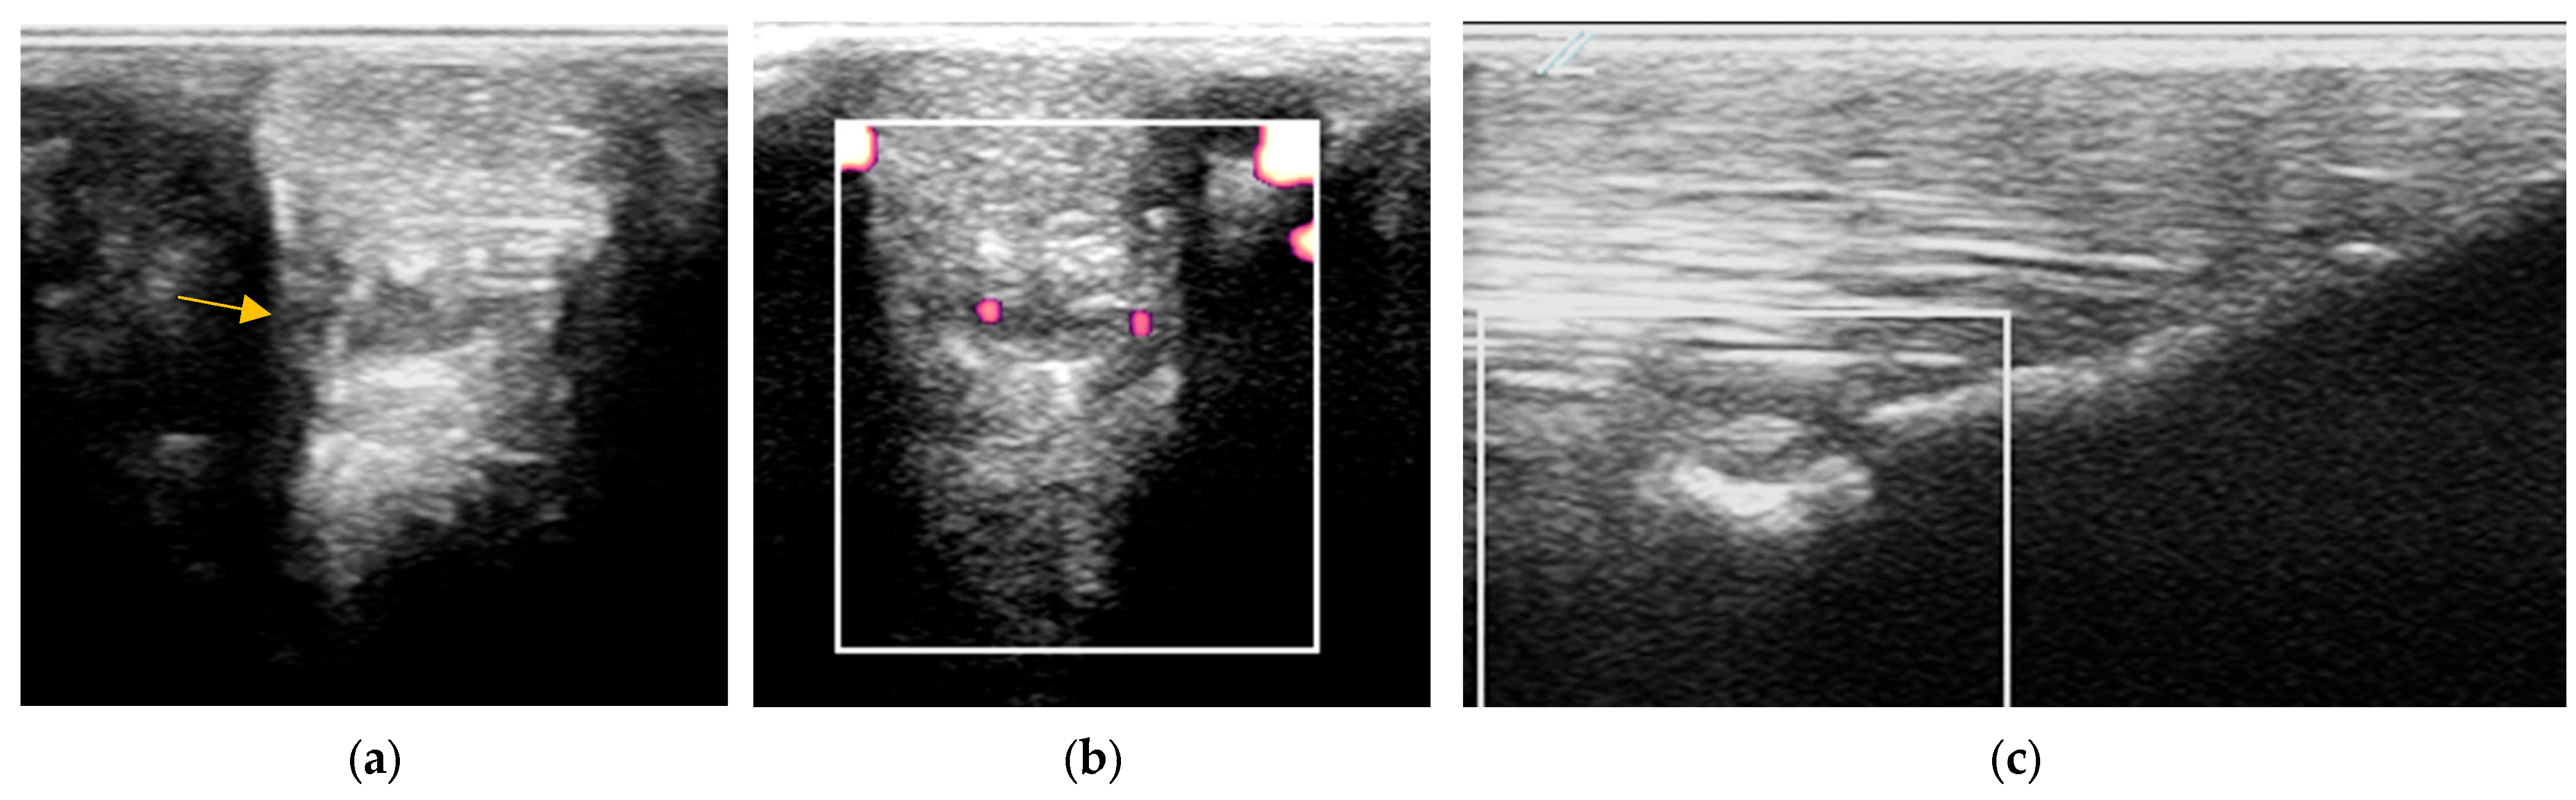

Figure 6. Twelve-year-old Warmblood mare with right hindlimb lameness and abduction of the limb during protraction. (a) Transverse, (b) longitudinal (distal to the right) and (c) transverse power Doppler images of the lateral branch of the suspensory ligament. There is a linear hyperechoic region causing acoustic shadowing. There is mild power Doppler signal localised around the hyperechoic region.

Figure 7. Transverse (left) and longitudinal (right) ultrasonographic images of the lateral branch of the suspensory ligament (SL) of a hindlimb of a 15-year-old purebred Spanish horse (PRE), acquired 2 weeks after injury, with a non-healing suspensory branch desmitis. The SL branch is enlarged with large hypoechoic regions and loss of long linear parallel echoes in the longitudinal image. There is also substantial subcutaneous echogenic tissue consistent with periligamentous fibrosis. Power Doppler signal was graded severe and persisted despite treatment. The horse was retired.